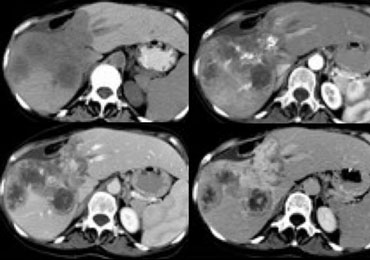

Large HCC with mozaik pattern in a non cirrhotic patient. Large HCC with mozaik pattern in a non cirrhotic patient.

Late appearance of HCC

HCC is a silent tumor, so if patients do not have cirrhosis or hepatitis C, you will discover them in a late stage.

They tend to be very large with a mozaic pattern, a capsule, hemorrhage, necrosis and fat evolution.

HCC becomes isodense or hypodense to liver in the portal venous phase due to fast wash-out. On delayed images the capsule and sometimes septa demonstrate prolonged enhancement.